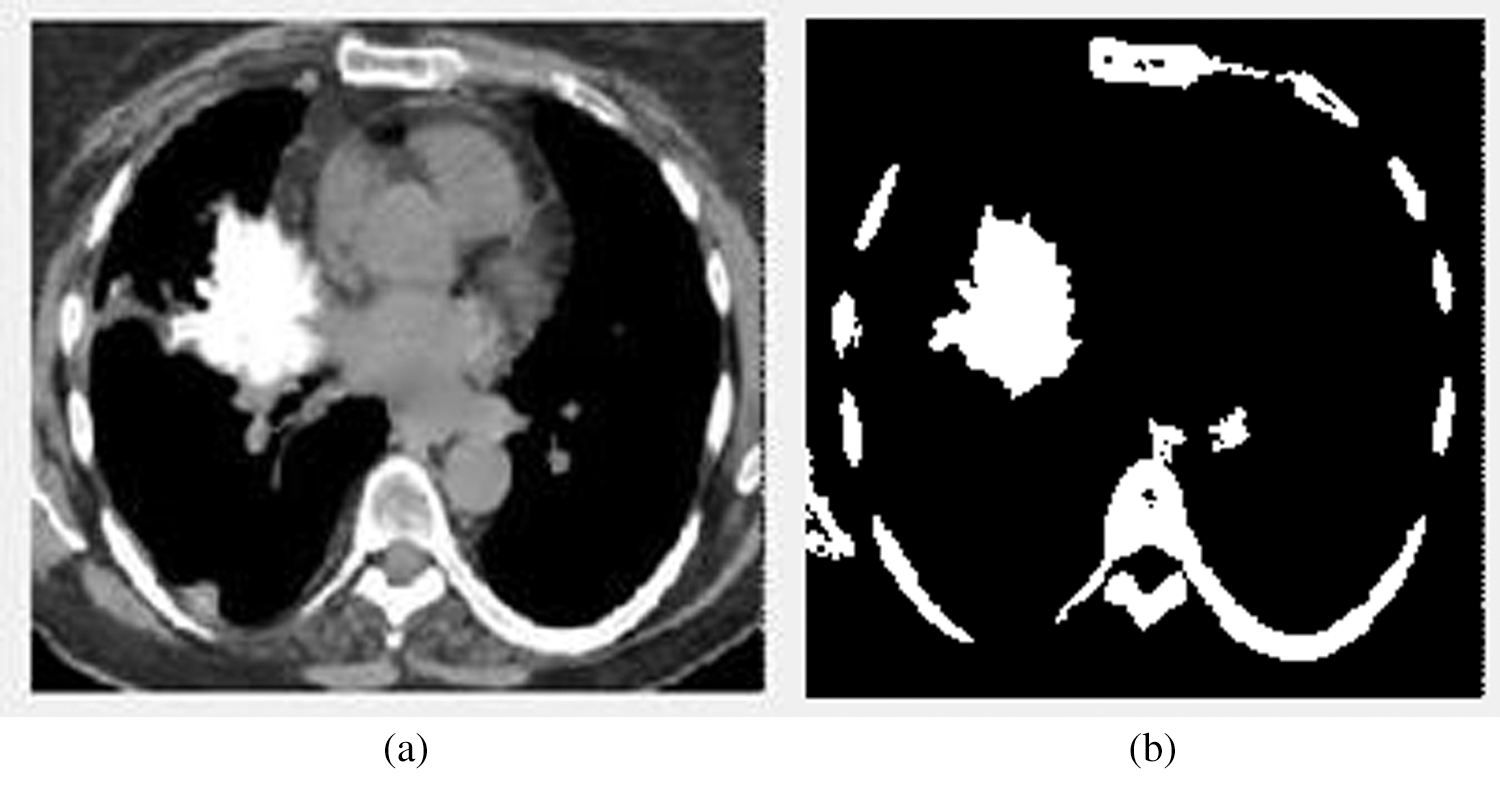

Figure 4: The input and output images of the segmentation stage. (a) The image before segmentation (b) The image after segmentation

Fig. 4 illustrates the input and output images of the segmentation stage. Fig. 4b denotes the affected area.